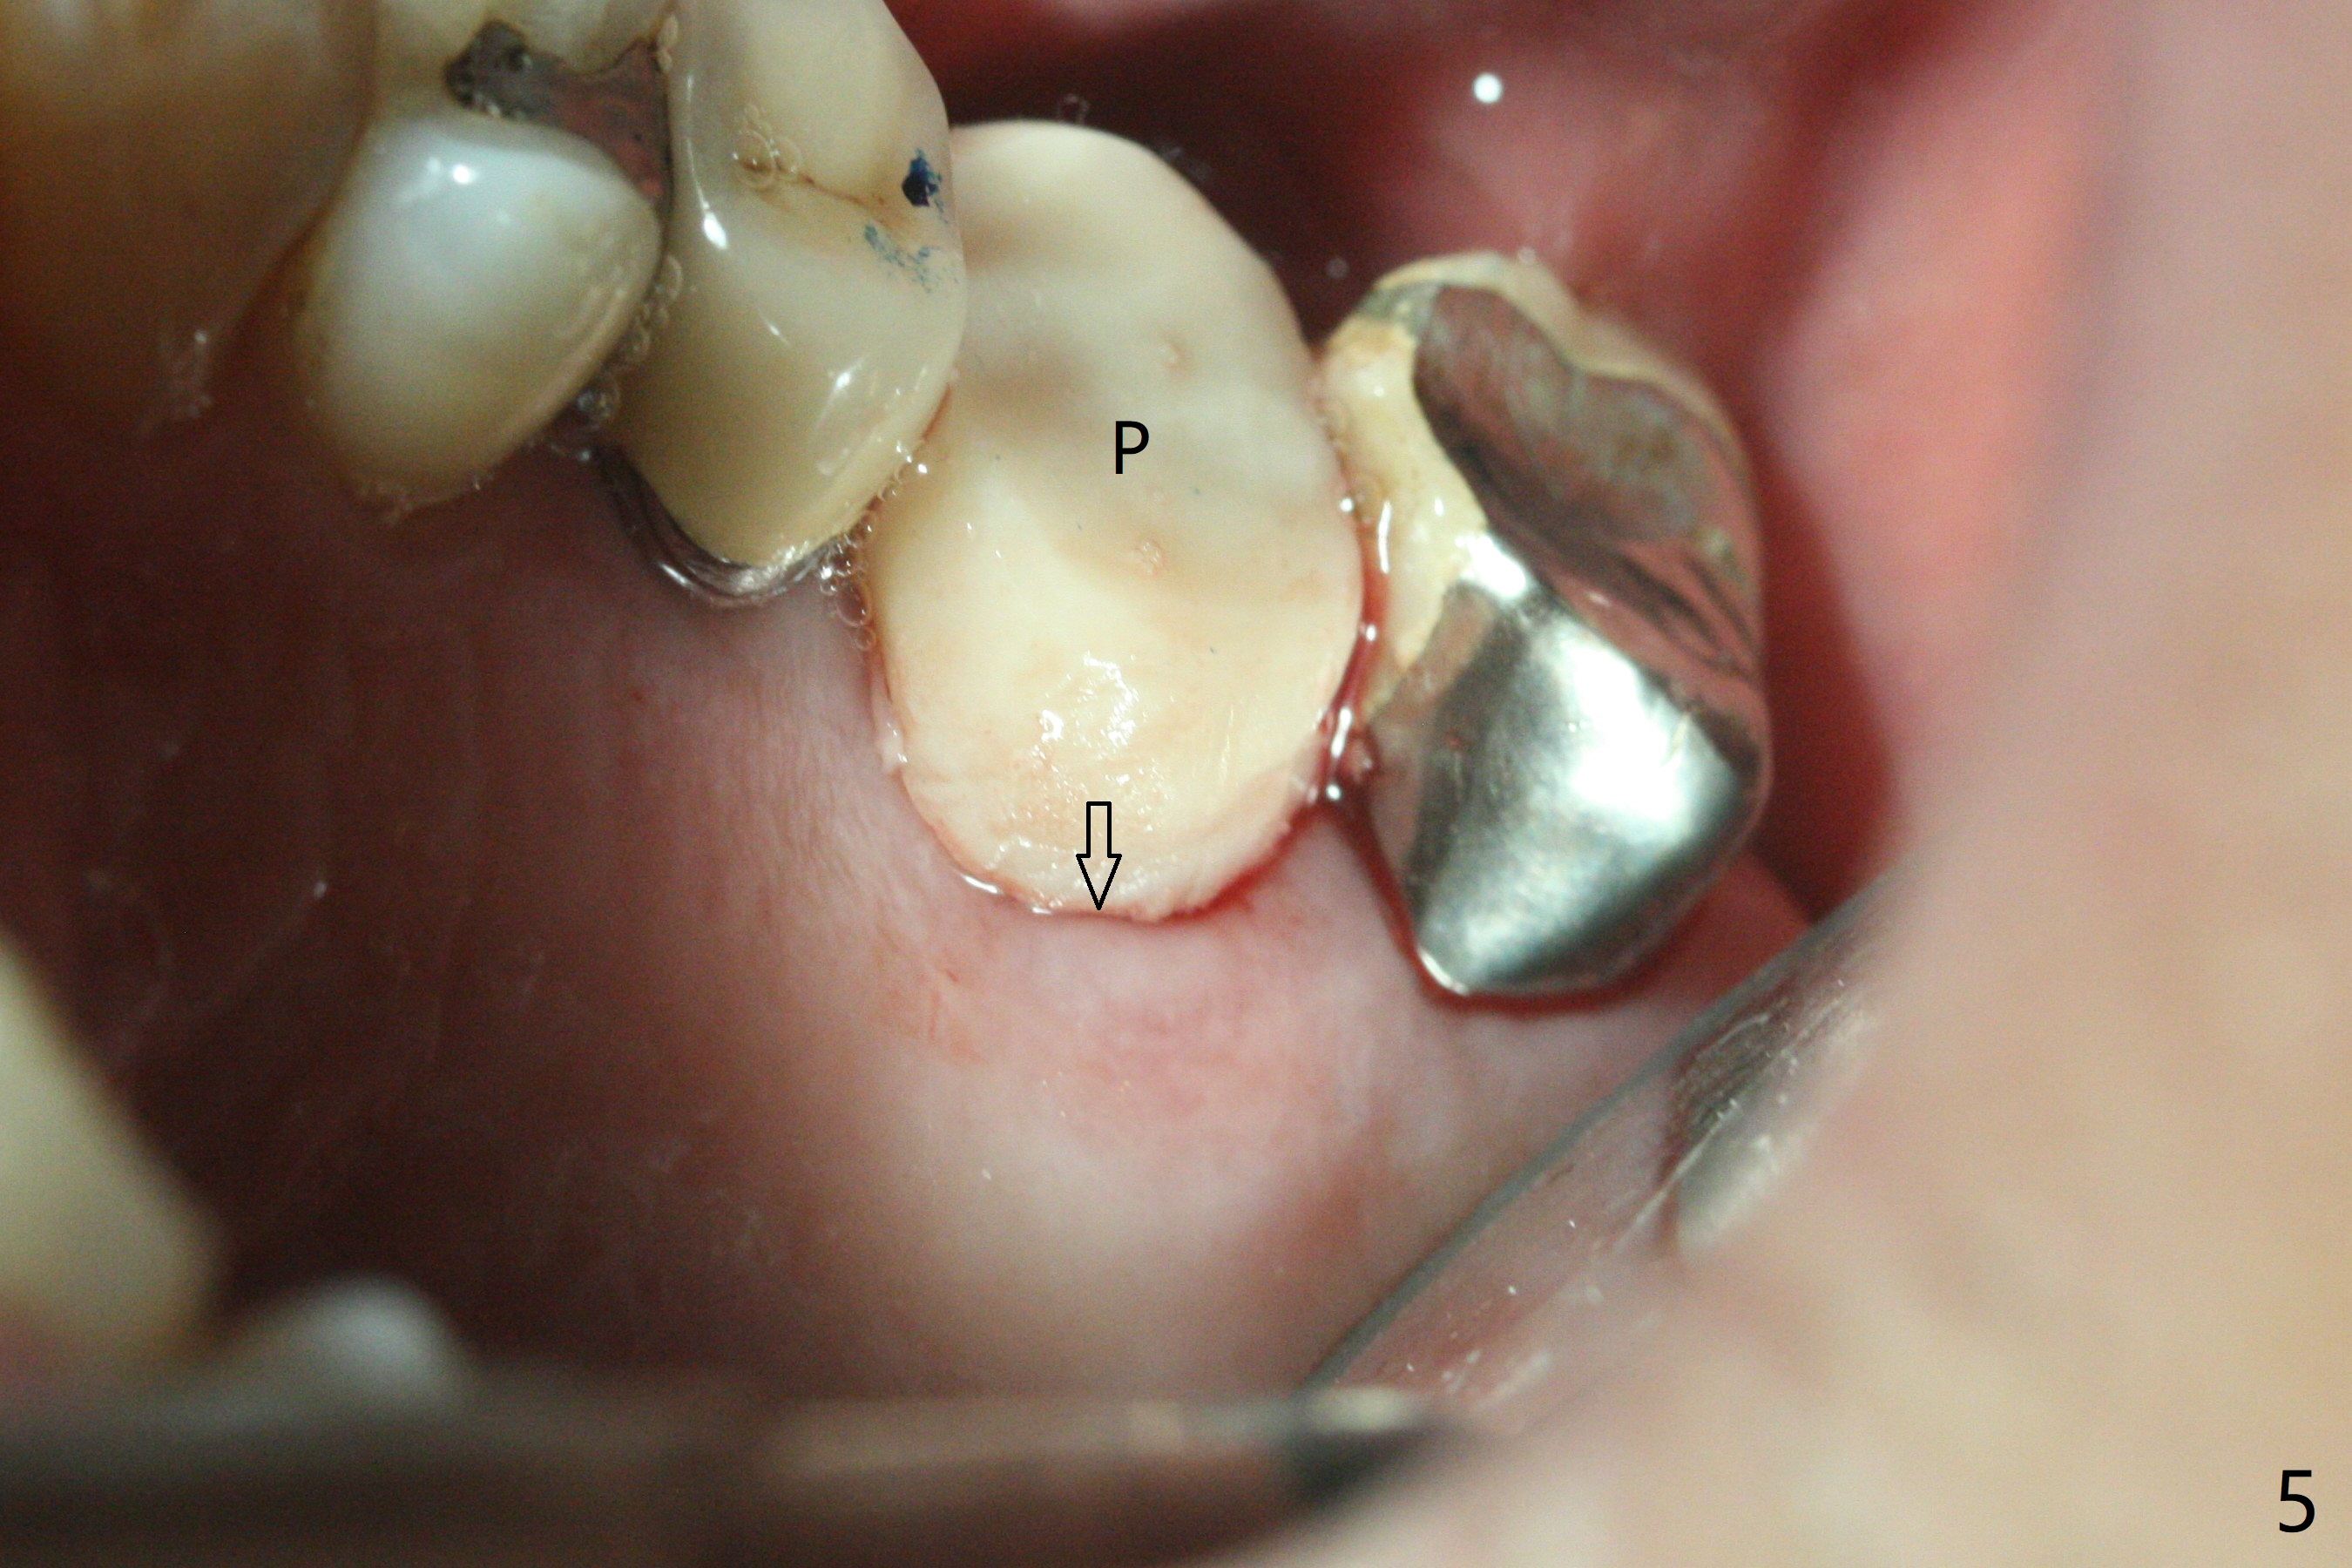

左上6腭侧退缩牙龈(图一:箭头)深部没有骨壁(图二:*),4.5x11毫米植体周围缺损(图三:*)由粘性骨粉(皮质骨,图四:*)填入,即刻临时牙冠(图五:P)覆盖腭侧缺损(空箭头)和PRF膜。临时牙冠颊腭侧做的很宽(图六),目的是关闭腭侧缺损,术后四周在不影响骨粉覆盖情况下,牙冠腭侧适当向颊侧缩小(图七:箭头),但是不应该缩短龈下边缘。术后四个月骨粉形态接近原位骨(图八),但是腭侧软硬组织仍有缺损,炎症。